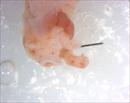

Caption: Mutant 2966-005-2 (E15.5) exhibits abnormal liver lobation.